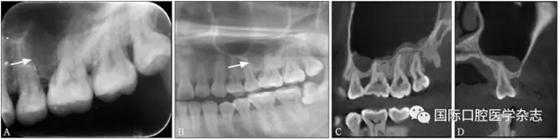

3.2 頦孔和切牙孔

因拍攝角度的不同,頦孔和切牙孔影像可能與根尖重疊(圖8),應注意觀察牙根的牙周膜及骨硬板是否連續(xù),或重新偏角拍攝X線片以確認其與牙根的關系。

圖 8 頦孔(A)和切牙孔(B)

Fig 8 Mental foramen(A) andincisive foramen(B)